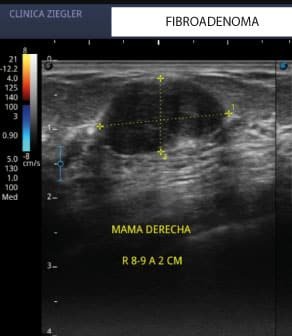

Imágenes Clave

• Ecografía: esencial para lesiones localizadas y para guiar biopsias.